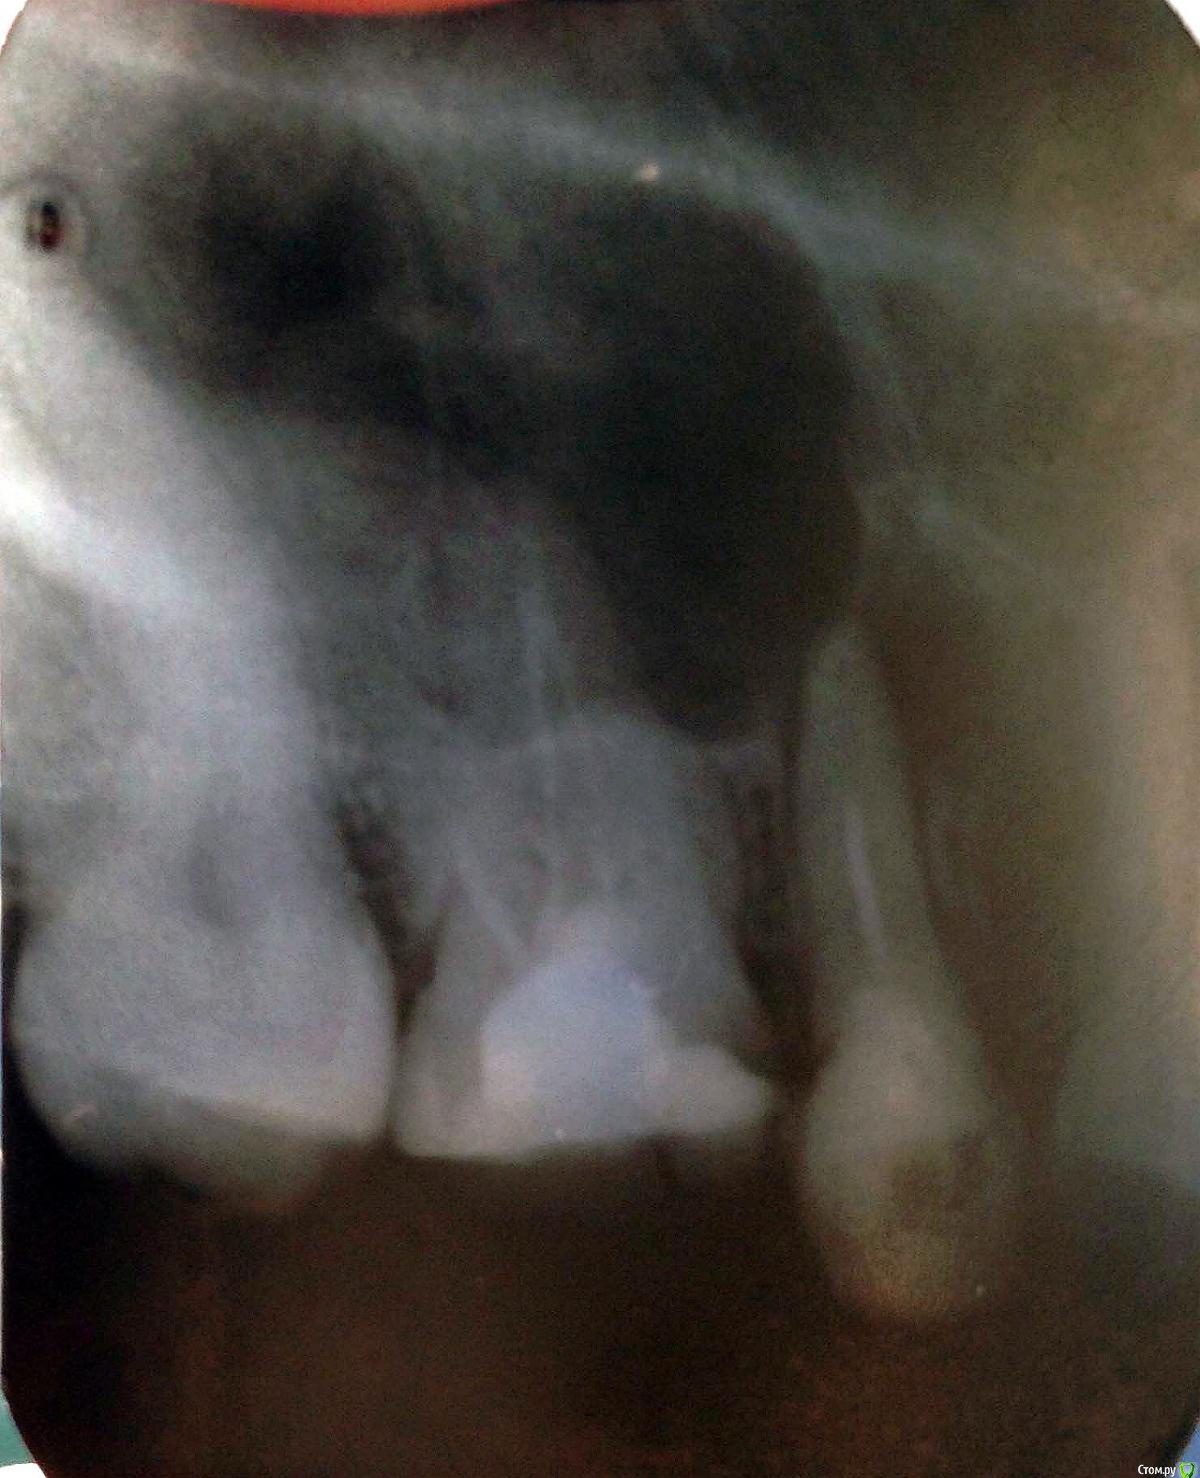

katrin12098 Опубликовано 15 августа, 2015 Поделиться Опубликовано 15 августа, 2015 (изменено) Здравствуйте!Подскажите пожалуйста.Заболела верхняя пятерка,пошла на прием к стоматологу сделали снимок сказали киста и нужно удалять в стационаре,так как зуб находиться рядом с гайморовой пазухой в поликлинике удалять отказались. Пропила пять дней амоксиклав зуб перестал беспокоить, насколько велика вероятность перфорации гайморовой пазухи и возможно ли удалить в клинике или всё же лучше обратиться в больницу в челюстно лицевую хирургию и удалить там? и какие могут быть осложнения? и возможно ли сохранить зуб? Изменено 15 августа, 2015 пользователем katrin12098 Ссылка на комментарий

Bier Опубликовано 16 августа, 2015 Поделиться Опубликовано 16 августа, 2015 а вообще похоже на то, что и удалять зуб не нужно, а можно вылечить. 2 Ссылка на комментарий

St. Опубликовано 16 августа, 2015 Поделиться Опубликовано 16 августа, 2015 Верхние пятый и шестой можно попробовать перелечить каналы и наблюдать. Если там нет трещин большая вероятность, что воспаление после качественной эндодонтии пройдет.Верхний шестой справа и центральный резец справа тоже необходимо перелечить каналы. И подумать о имплантации в области отсутствующего на нижней челюсти. Ссылка на комментарий